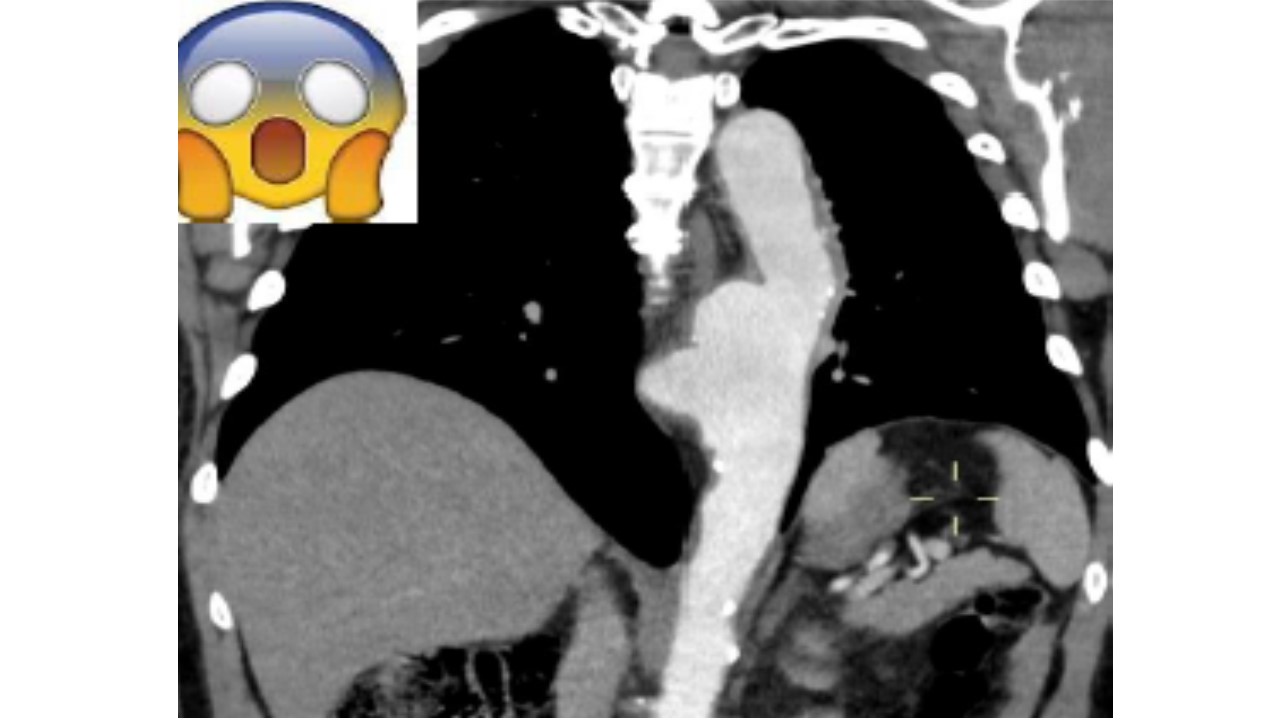

SINDROME HEPATOPULMONAR (SUGERIDA POR IMAGEM): BELO CASO

Imagem 2